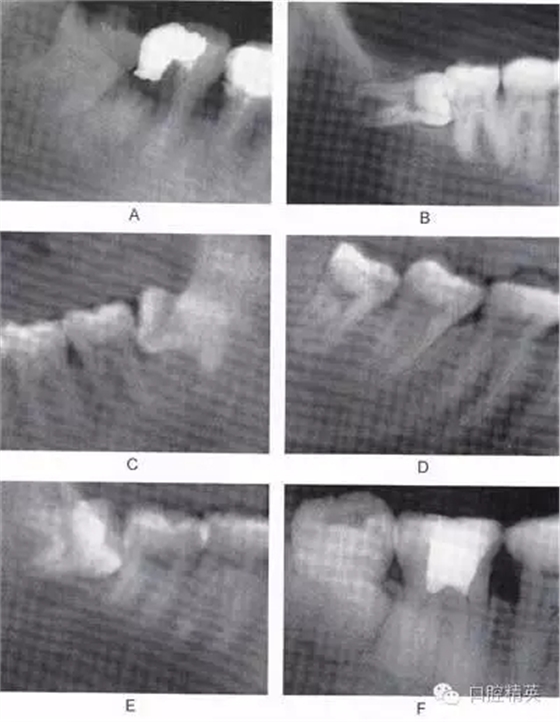

圖6-2 根據(jù)阻生牙相對于下頜升支前緣位置關(guān)系分為:第1類 (圖A):下頜升支前緣和第二磨牙遠(yuǎn)中面之間有足夠的間隙容 納第三磨牙牙冠;第2類(圖B):約一半的第三磨牙牙冠被下 頜升支前緣覆蓋;第3類(圖C):第三磨牙全部位于下頜升支 前緣內(nèi)

A

B

C

圖6-3 相對于聆平面的位置關(guān)系分為:A分類(圖A):第三磨牙殆面平齊于第二磨牙聆面;B分類(圖B):第三磨牙(牙合)面 位于第二磨牙殆面和牙頸部平面之間;C分類(圖C):第三磨牙(牙合)面低于第二磨牙的牙頸部平面。一般情況下,近中阻生拔除難度比垂直阻生小,垂直阻生比水平阻生小,水平阻生比遠(yuǎn) 中阻生小;第1類比第2類簡單,第2類比第3類簡單;A分類比B分類簡單,B分類比C分類簡單。另外拔牙難度與牙齒形態(tài)、 患者年齡、牙周骨質(zhì)密度以及與下牙槽神經(jīng)管的關(guān)系也有關(guān)聯(lián)。 骨質(zhì)密度越大,年齡越大,患牙牙周骨質(zhì)鈣化程度越高,越難拔除.

G、H

圖6-4 以上類型的下頜第三磨牙由于根阻力大,一般需要分根才能拔除

A.多根牙 B。超長根 C。牙根向遠(yuǎn)中彎曲 D。兩根環(huán)抱 E。根分叉大 F,根端肥大 G。彎根 H.U型根(X線片及離體牙)